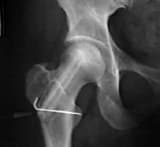

A 45 year-old lady has been having severe pain near her right hip joint for the last 30 years as a result of which she finds walking painful. She was diagnosed as a case of avascular necrosis of the femur head.

“The amount of disability that results from avascular necrosis depends on what part of the bone is affected, how large an area is involved, and how effectively the bone rebuilds itself. The process of bone rebuilding takes place after an injury as well as during normal growth. Normally, bone continuously breaks down and rebuilds—old bone is reabsorbed and replaced with new bone. The process keeps the skeleton strong and helps it to maintain a balance of minerals. In the course of avascular necrosis, however, the healing process is usually ineffective and the bone tissues break down faster than the body can repair them. If left untreated, the disease progresses, the bone collapses, and the joint surface breaks down, leading to pain and arthritis.“